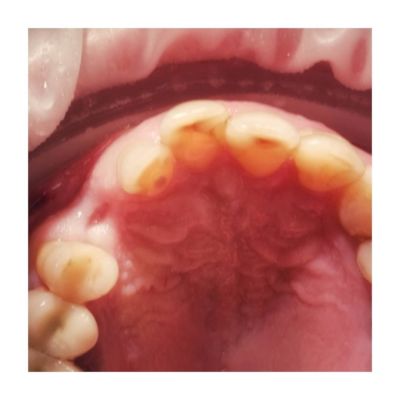

Pacjent zostaje przygotowany do zabiegu i przebrany w zestaw sterylnej odzieży (zachowanie zasad aseptyki i antyseptyki). Lekarz znieczula nasiękowo (miejscowo) okolicę, gdzie ma być wprowadzony implant. Wykonywane jest nacięcie błony śluzowej i odsłonięcie kości.

Następnie używając zestawu specjalnych wierteł zostaje przygotowane tzw. łoże dla implantu i wprowadzany jest implant. Zostaje założona śruba zamykająca. Płat śluzówkowo – okostnowy zostaje zaszyty.